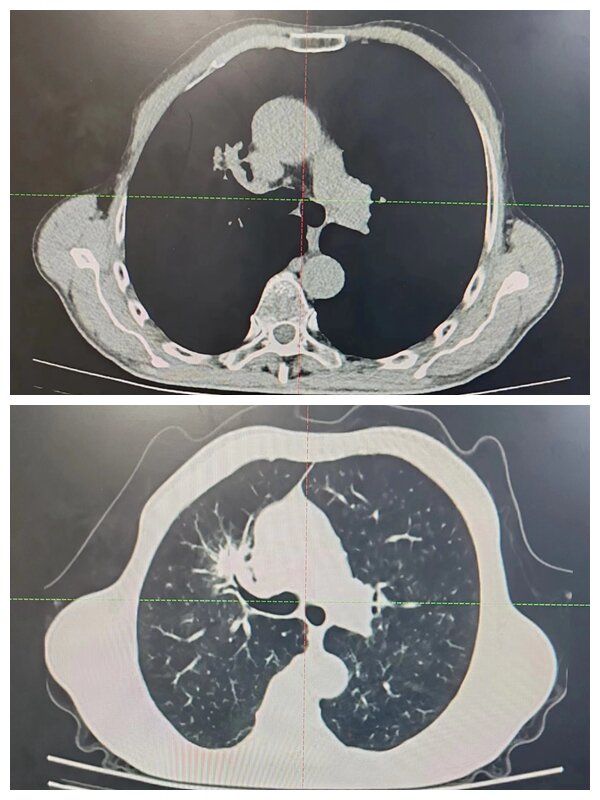

放療前

“超分割”放療治療前,需要讓患者保持一個(gè)輕松舒適的仰臥位,用熱塑膜固定,通過(guò)增強(qiáng)CT掃描并上傳至計(jì)劃系統(tǒng),并勾畫病灶和周圍正常器官。放療科物理師和醫(yī)生制定治療計(jì)劃并評(píng)估,之后通過(guò)三維劑量驗(yàn)證設(shè)備,做劑量驗(yàn)證,然后行治療前圖像引導(dǎo),從而保證了治療靶區(qū)的精準(zhǔn)性、位置的準(zhǔn)確性及劑量的準(zhǔn)確性。